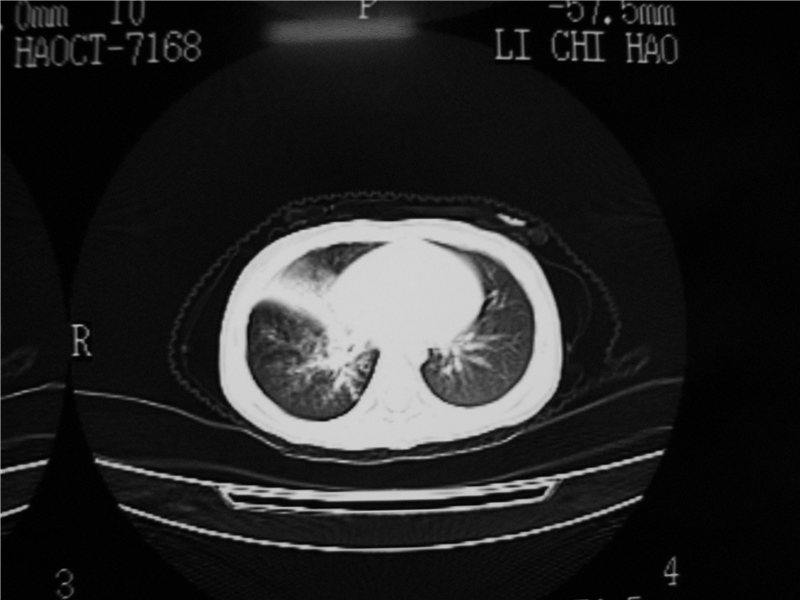

标题: PED3236:男2岁进食花生米后发烧10天。

右侧中间段支气管阴性异物可能,建议支气管镜

1)右肺炎症并右肺中叶肺不张,右肺上叶充气不良。2)右侧支气管异物不排除。

结合病史,考虑气管异物所致。

再有,我们16排ct有气管重建功能,肯异物效果可以。